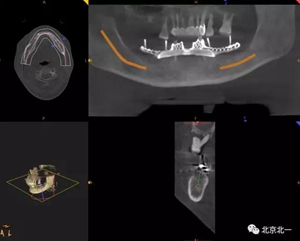

圖一:術(shù)前CBCT

圖二:術(shù)前數(shù)字化設(shè)計(jì)種植導(dǎo)航手術(shù),設(shè)計(jì)導(dǎo)板

圖二:術(shù)前模擬導(dǎo)板 , 精準(zhǔn)植入。